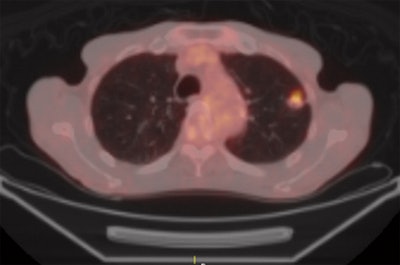

| Axial images of primary lung cancer (adenocarcinoma) in left upper lung lobe in 76-year-old man. Above, thin-section CT image shows nodule 18 mm in diameter in left upper lobe. Below, perfusion map shows nodule has high perfusion, with PFMS (scale at left) determined to be 89.9 mL/100 mL/min; this is a true-positive case according to maximal slope method results. Bottom, integrated PET/CT image shows high uptake of FDG, with SUVmax of lesion determined to be 3.8, indicating a true-positive case. Images republished with permission of the Radiological Society of North America from Radiology, February 2011, Vol. 258:2, pp. 599-609. |